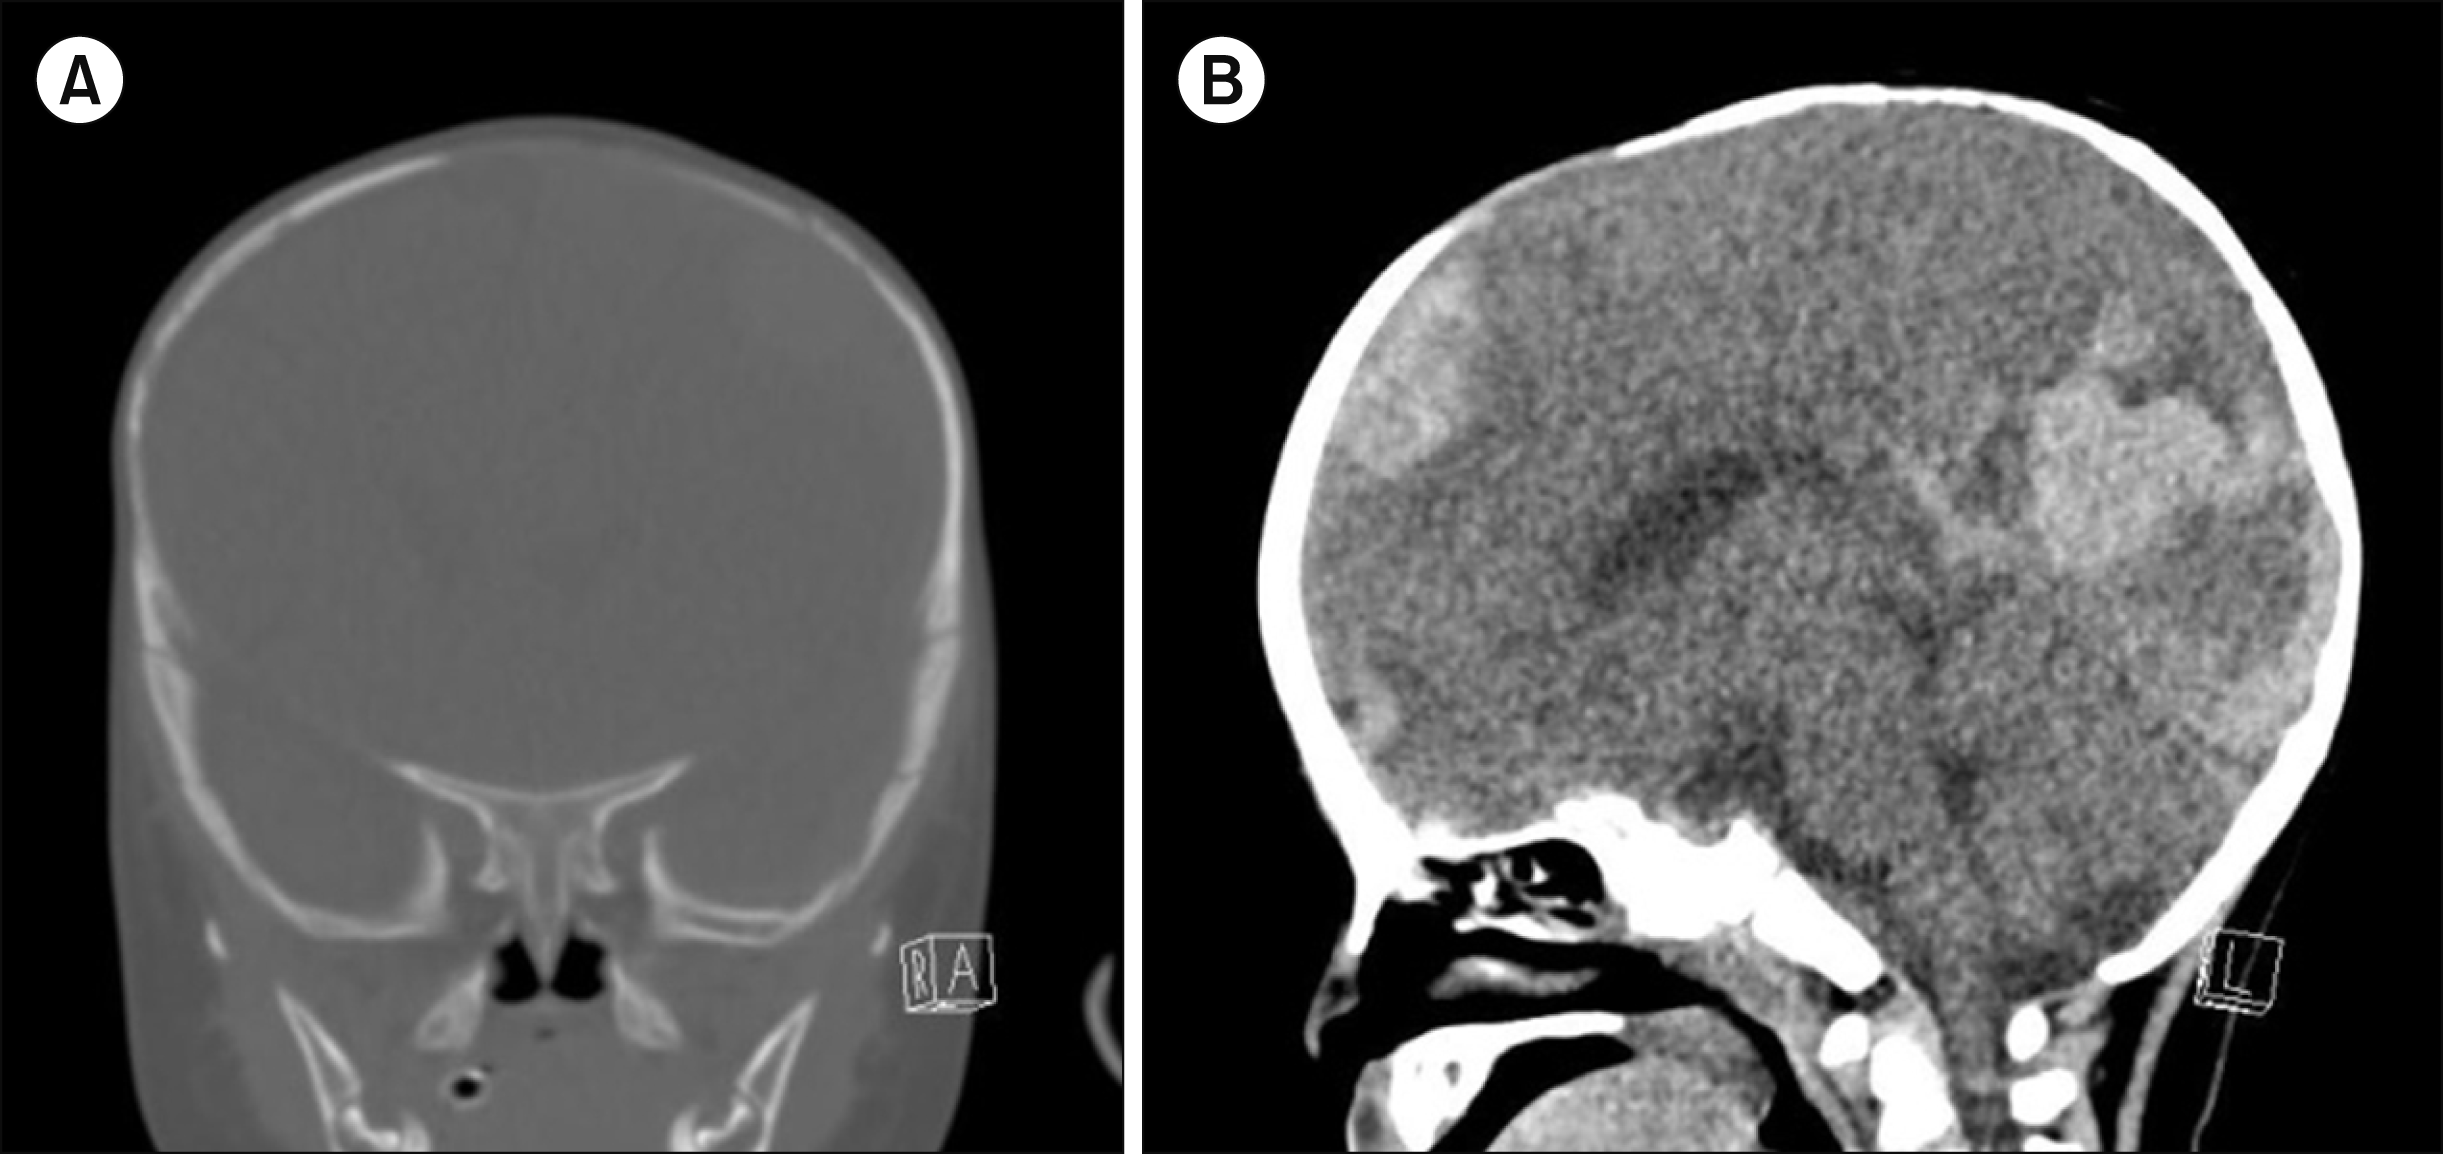

An 8-month-old male infant visited the emergency room for status epilepticus with stupor and prolonged fever. Initial vital signs were as follows: blood pressure, 70/40 mmHg; heart rate, 182 beats/min; oxygen saturation, 56%; and body temperature, 39.1°C. Initial laboratory tests revealed the following: pH, 7.147, (reference, 7.32–7.41); pCO2, 73 mmHg (reference, 42–52 mmHg); white blood cell count, 27.63× 109/L (reference, 6–15×109/L); hemoglobin, 6.4 g/dL (reference, 10.5–14.0 g/dL); mean corpuscular volume, 79.8 fL (normal value at 8 mo, 70 fL); mean corpuscular hemoglobin level, 24.3 pg (normal value at 8 mo, 23 pg); platelet count, 875×109/L (reference, 130–400×109/L); prothrombin time (PT), 14 s (reference, 10–14 s), and activated partial thromboplastin time (aPTT), 86.4 s (reference, 20.0–33.5 s); C-reactive protein level, 13.2 mg/dL (reference, <0.5 mg/dL); erythrocyte sedimentation rate, 86 mm/h (reference, 0–15 mm/h); aspartate transaminase level, 113 U/L (reference, 22–63 U/L); and alanine transaminase level, 56 U/L (reference, 12–46 U/L). Computed tomography of the brain without contrast was performed because of severe anemia, which revealed fractures of the left temporal and parietal bones (Fig. 1A), acute epidural hematoma along the entire left hemisphere and falx cerebri, multifocal hemorrhagic contusion of the left cerebral hemisphere, associated subfalcine herniation, and brain edema (Fig. 1B). There were no significant wounds or bruises other than two on the forehead and chest, which were caused by bumping into a friend while playing. Imaging tests revealed skull fractures with ICH; thus, police investigations for child abuse were initiated. Police investigation was conducted according to the standard protocol of the hospital for pediatric patients with ICH. The medical staff was involved in administering only medical treatment to the patient, which ensured good rapport with the patient’s parents.

Fig. 1

Computed tomography of brain in an infant with severe hemophilia A with intracranial hemorrhage mistaken to be caused by child abuse. (A) Left temporal and parietal bone fractures. (B) Acute epidural hematoma along the entire left hemisphere and falx cerebri, multifocal hemorrhagic contusion of left cerebral hemisphere, associated subfalcine herniation, and brain edema.